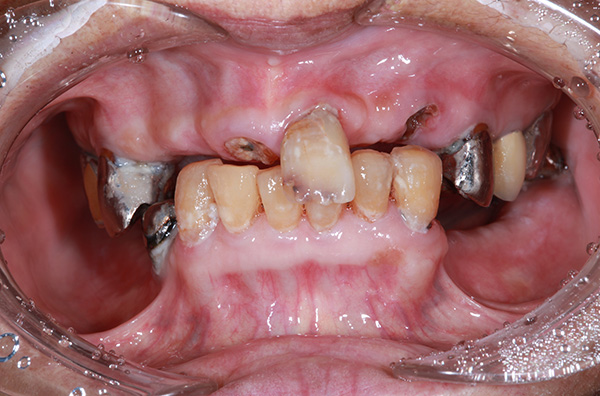

このようなお悩みはございませんか?

- 歯がボロボロで恥ずかしくて歯医者に行けない

- 歯がボロボロで人前で口を開けて笑えない

当院は歯がボロボロの方でも大歓迎です!!

歯がボロボロになったことには、きっと何らかの理由があると思っています。